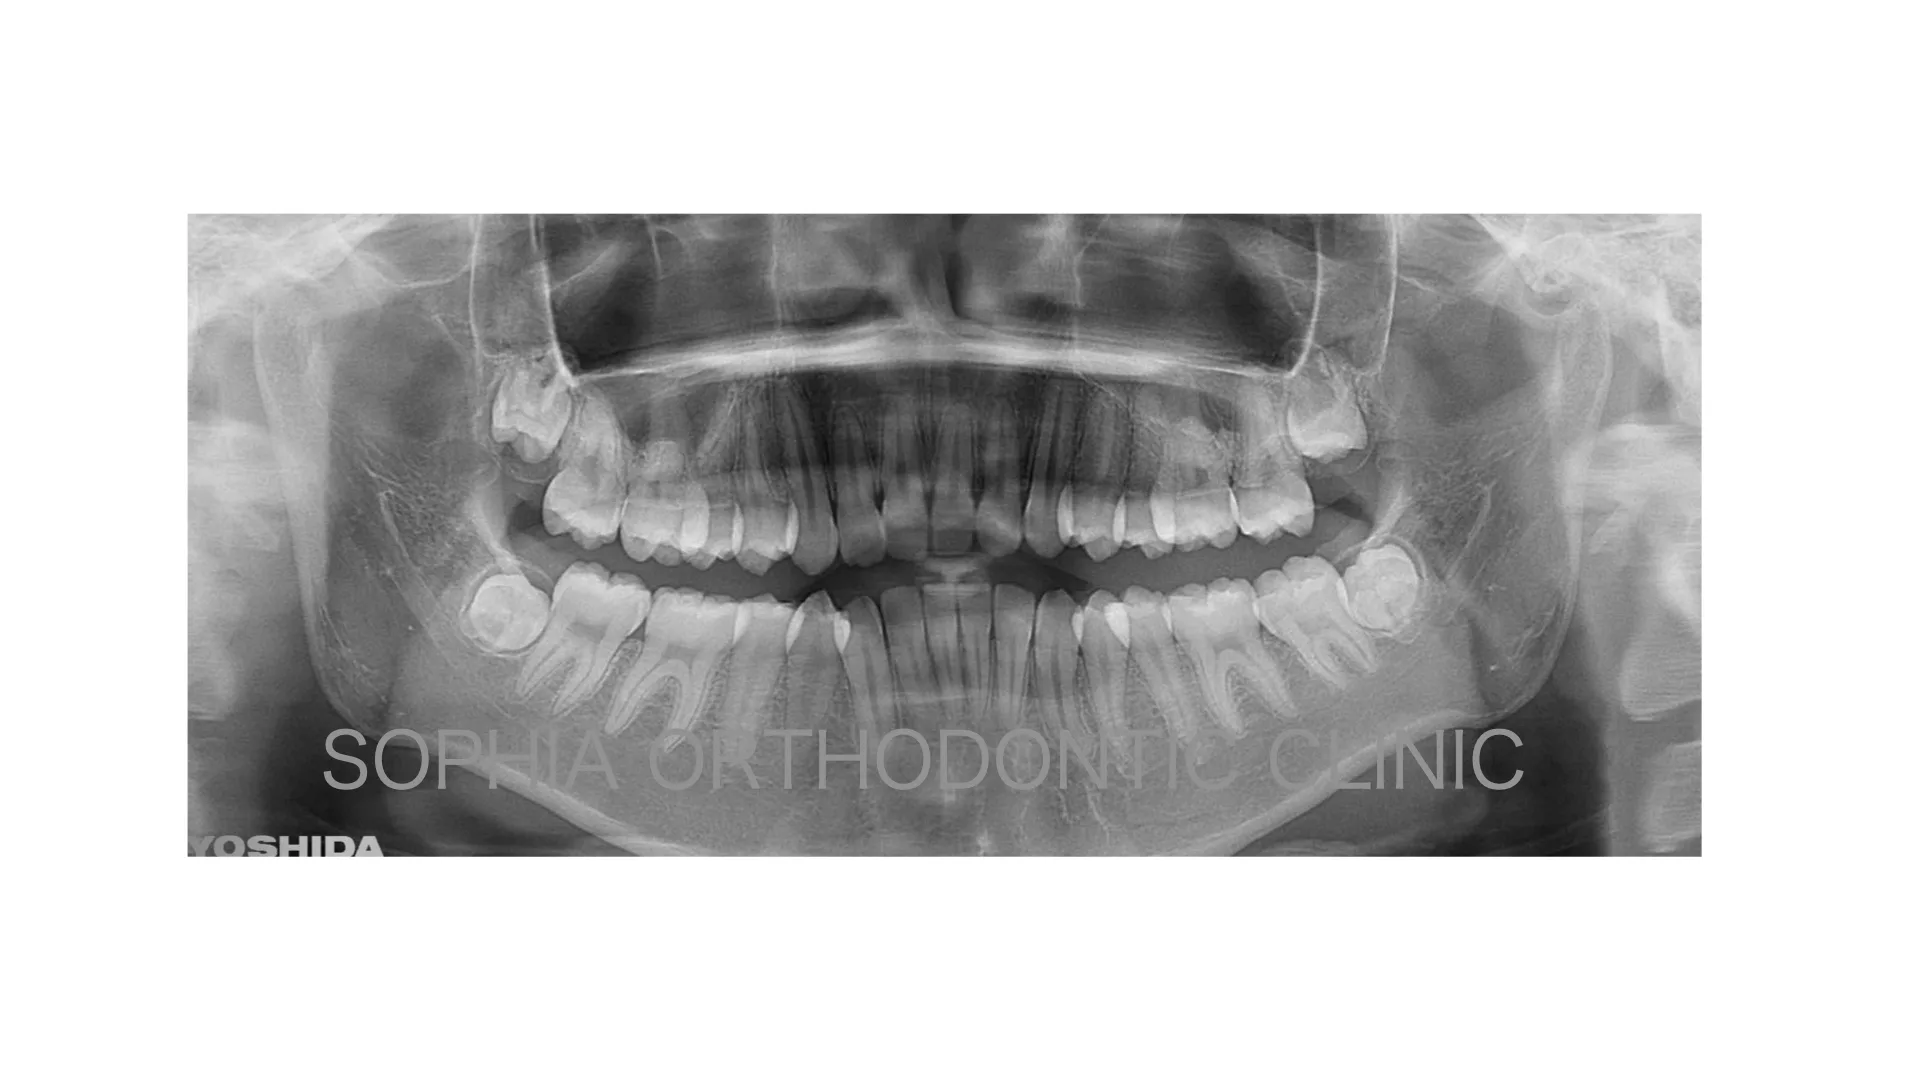

症例 上顎前突 抜歯